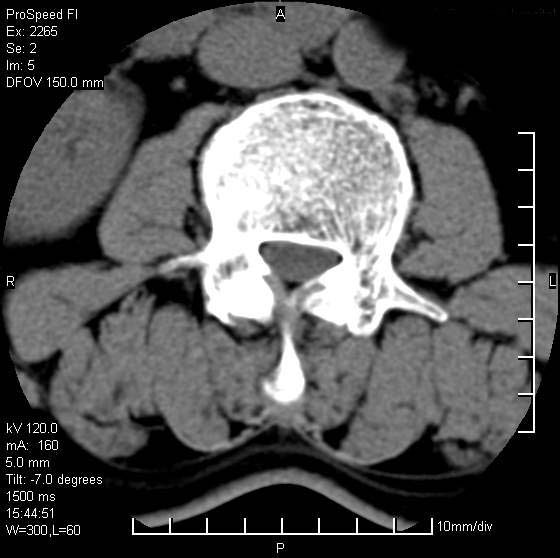

以下是引用qiushi在2007-8-22 17:26:00的发言:[br]没骨窗![br] 1、 l5~s1间盘膨出伴轻度突出(中央型)、变性。[br] 2、l4~5间盘膨出伴突出(右侧远外侧型)。[br] 3、l3~4间盘膨出。[br] 4、腰椎退行性变。[br]

以下是引用随缘的人在2007-8-22 20:56:00的发言:[br]腰椎退行性变:1。l4/5,l5/s1膨出[br] 2。l5/s1间盘退行性变 [br] 3。腰椎骨质增生

以下是引用liaizhi在2007-8-22 22:13:00的发言:[br]1,l4-5锥间盘膨出,2,l5-s1椎间盘膨出并退变(椎间盘呈真空征);3,血管瘤(椎体骨小梁稀疏粗大)?